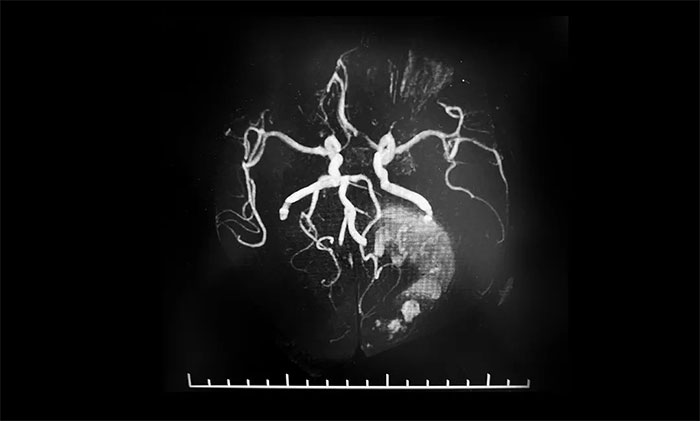

▲ 術前MRA,了解腫瘤供血情況

術前,潘仁龍主任給予患者脫水劑、白蛋白、甘露醇等藥物治療,患者病情逐漸穩(wěn)定,可以睜眼,身體相關指標達到手術條件。為了進一步降低手術風險,李士其教授等專家團隊進行了詳細的術前準備,包括手術設計、切口大小設計、手術備血等。同時,術前進行了磁共振血管成像,詳細了解腫瘤供血情況,確保手術可控,萬無一失。